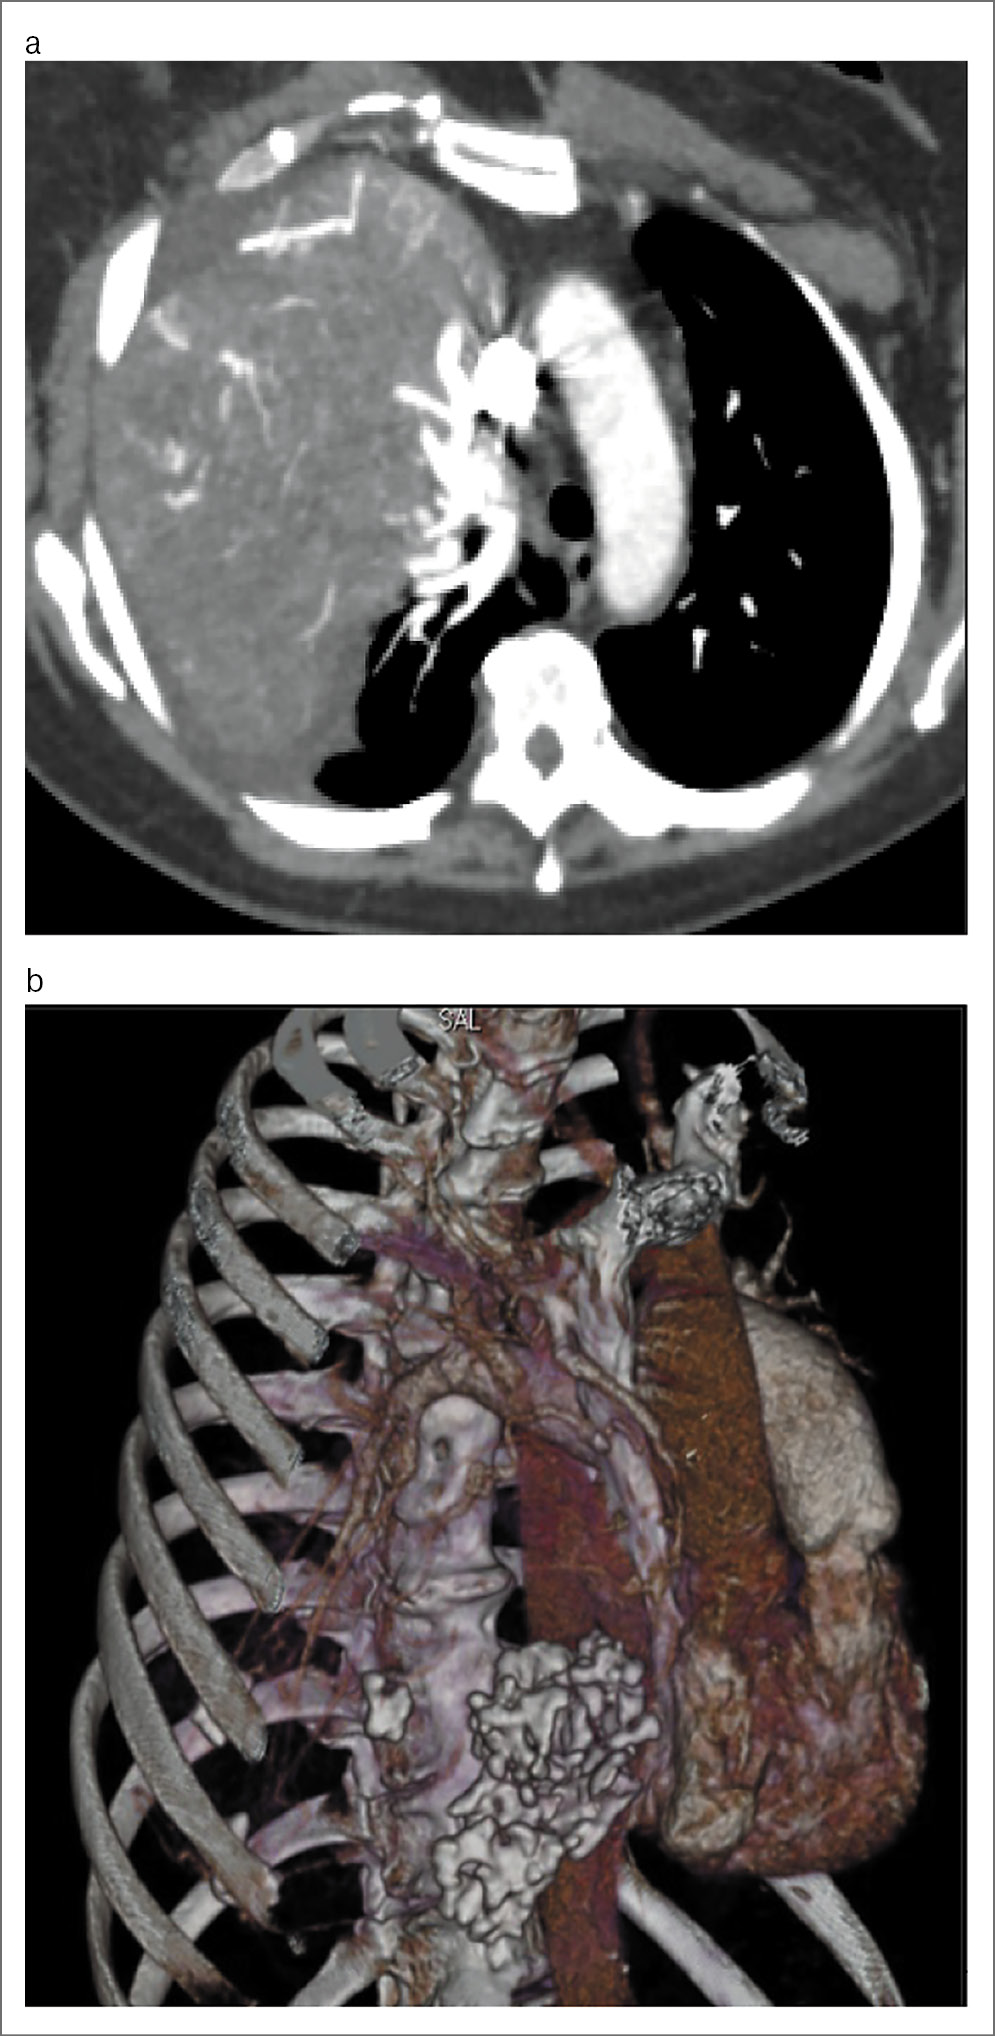

Пациент Л., 76 лет. Диагноз: рецидив новообразования (невринома) заднего средостения, осложненная компрессией правого легкого, сердца, магистральных сосудов, трахеи, пищевода. Жалобы на одышку при умеренной физической нагрузке, выраженную одышку в положении лежа, на дискомфорт и чувство тяжести в грудной клетки. Анамнез: в 2010 г. выполнена экстирпация невриномы заднего средостения. При динамическом наблюдении данных в пользу рецидива заболевания не отмечено. В середине 2017 г. у пациента появилась одышка, усиливающаяся в положении лежа. При МСКТ выявлено образование заднего средостения больших размеров, смещающее структуры средостения кпереди. При контрастировании признаков инвазии легочных сосудов, аорты и перикарда не выявлено (рис. 7, a–d).

Рис. 7. а, b – аксиальная проекция: визуализируется образование в заднем средостении, смещающее трахею, легочные сосуды, массив сердца кпереди; c, d – МПР: при контрастировании признаков инвазии структур средостения не выявлено.

С учетом данных КТ-исследования с контрастированием определен вариант оперативного вмешательства: торактомия справа, удаление опухоли заднего средостения (рис. 8, a–c).